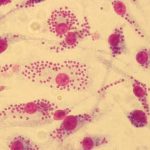

Study: Researchers in medicinal chemistry and parasitology develop an innovative strategy to identify leishmanicidal...

Leishmania is a microorganism that enters the human body via a sandfly bite. Instead of fleeing the white blood cells deployed by the...